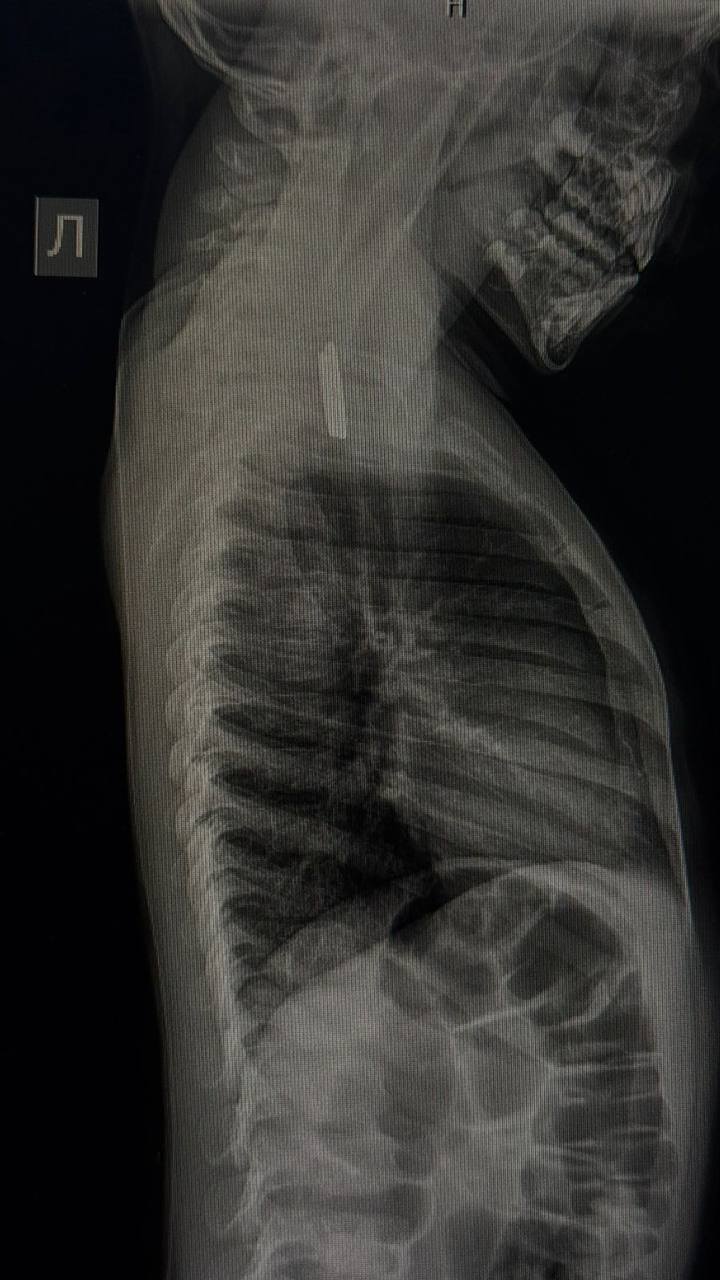

В Национальный центр медицины Якутии госпитализировали трехлетнего ребенка, проглотившего монеты номиналом пять и десять рублей. Инородные тела застряли в верхней трети пищевода, сообщает ЯСИА.

Мальчика беспокоили кашель и обильное слюнотечение. Экстренную операцию провела врач-эндоскопист, заведующая эндоскопическим отделением РБ № 1 – НЦМ Мария Еремеева.

«Родители обратились в больницу в тот же день, когда ребенок проглотил монеты. Инородные тела были обнаружены в верхней трети пищевода. Операция прошла успешно, сложностей при извлечении монет не возникло. После операции ребёнок в удовлетворительном состоянии остался под наблюдением в хирургическом отделении», — рассказала ЯСИА Мария Еремеева.